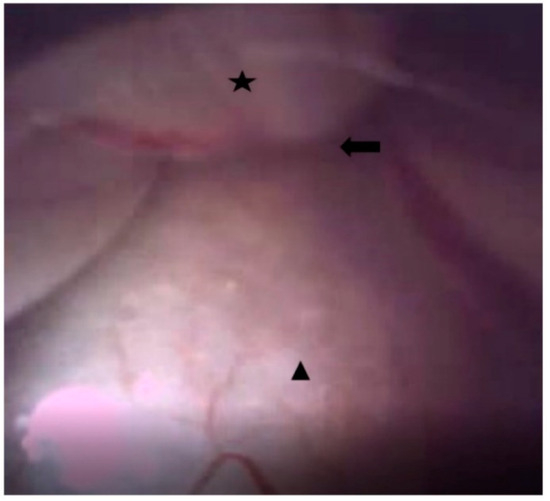

2.4. Endoscopic Epidural Neuroplasty